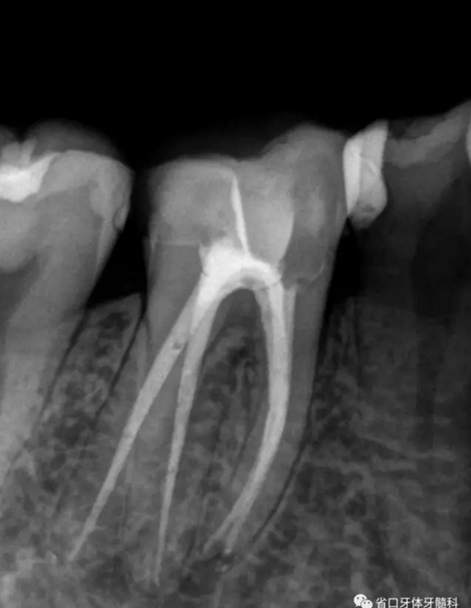

圖1 術前X線片:46/近中根面繼發(fā)齲,根尖周低密度影,遠中舌側(cè)根管影像模糊;根分叉低密度影,近中牙槽骨見少許角形吸收。

處置:46/上橡皮障,顯微鏡下去齲、開髓、拔髓、探根管口4個。其中ML鈣化明顯,ET40蕩洗,導入EDTA輔助疏通細小彎曲ML,測長:22mm。鎳鈦預備根管,根尖寬度備至25#,超聲蕩洗,紙尖干燥,AH-plus+熱牙膠垂直加壓充填,GIC暫封。

圖2 術后根充片